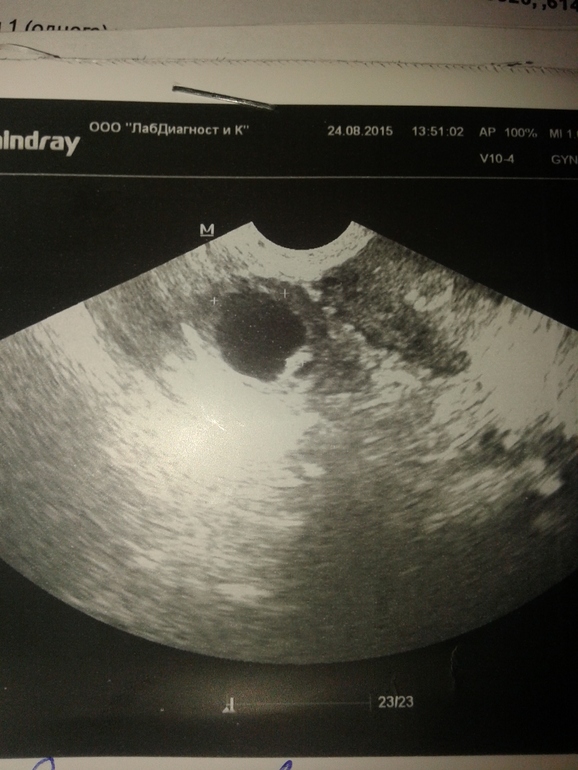

Как будто недоовулировал. У меня такое было. Дф открылся и закрылся, часть содержимого вышла. По краям зернисто, внутри однородночерно

Больше на фолликул похоже, жт как заездочка, в том плане что края не ровные

мне кажется это фоликул..больно круглый

желтое тело немного не такое...

а какого размера этот кругляшок?